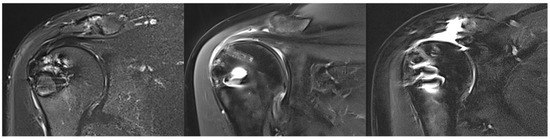

3.5. Tendon Healing

At FU12, MRI confirmed satisfactory and complete tendon healing in 17 patients (56.7%) classified as Sugaya type 1 (11 patients, 36.7%) and Sugaya type 2 (6 patients, 20.0%). Partial tendon healing, classified as Sugaya type 3, was observed in 5 patients (16.7%). Insufficient tendon healing was found in 8 patients (26.7%) classified as Sugaya type 4 (2 patients, 6.7%) and Sugaya type 5 (6 patients, 20.0%). The rate of insufficient healing was 44.4% in the secondary repaired group and 19.0% in the primary repaired group (p = 0.20). There was no correlation between preoperative or intraoperative risk factors and retear at FU12. Moreover, there were no significant differences in clinical outcomes between healed and non-healed SSP tendons, with both cohorts demonstrating significant improvement. Figure 4 provides example MRI images corresponding to Sugaya types 1, 3, and 5.

Figure 4. Illustration of supraspinatus tendon healing according to Sugaya. (Left): complete healing (Sugaya 1), (middle): unclear healing (Sugaya 3), (right): non-healing (Sugaya 5).